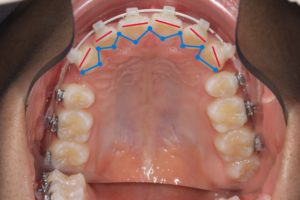

矯正治療前

赤い線が切端ライン

青い線が歯頚部ラインです。

抜歯後8カ月経過

唇側に向いていた切端ラインが

抜歯後内側(口蓋側)に向いています。

このように前歯を後退できるのは

精密検査時のCTデータで

骨の厚み、歯根の位置を立体的に把握し

前歯を下げても骨や歯肉に無理が生じないことを

事前に確認した上で治療を行うからです。